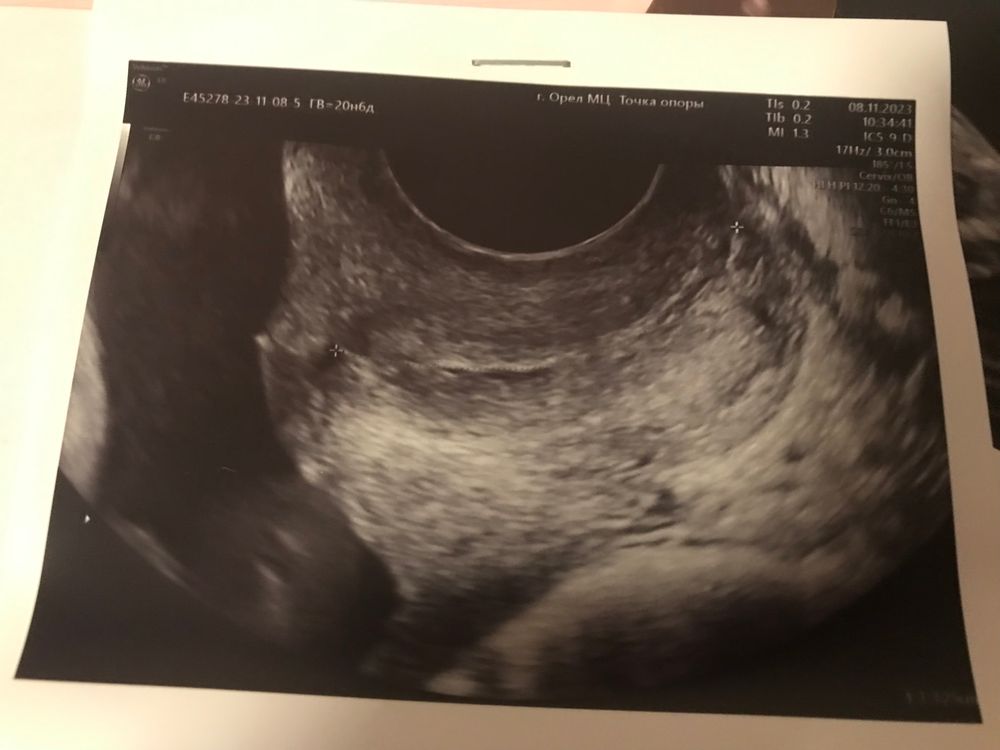

Здравствуйте девочки. Была сегодня на 2 скрине. По плоду 20 недель. Шейку намерили 32,5мм, внутренний зев закрыт. На первом скрине была 39мм. Сказали перемерить через 2 недели. Немного переживаю, я же плюс на утрике еше…почему укоротилась? Девочки, стоит ли переживать? Па с мужем не прекращали, и врач вроде не говорила воздерживаться. У кого было? Доходили без швов и пессария?